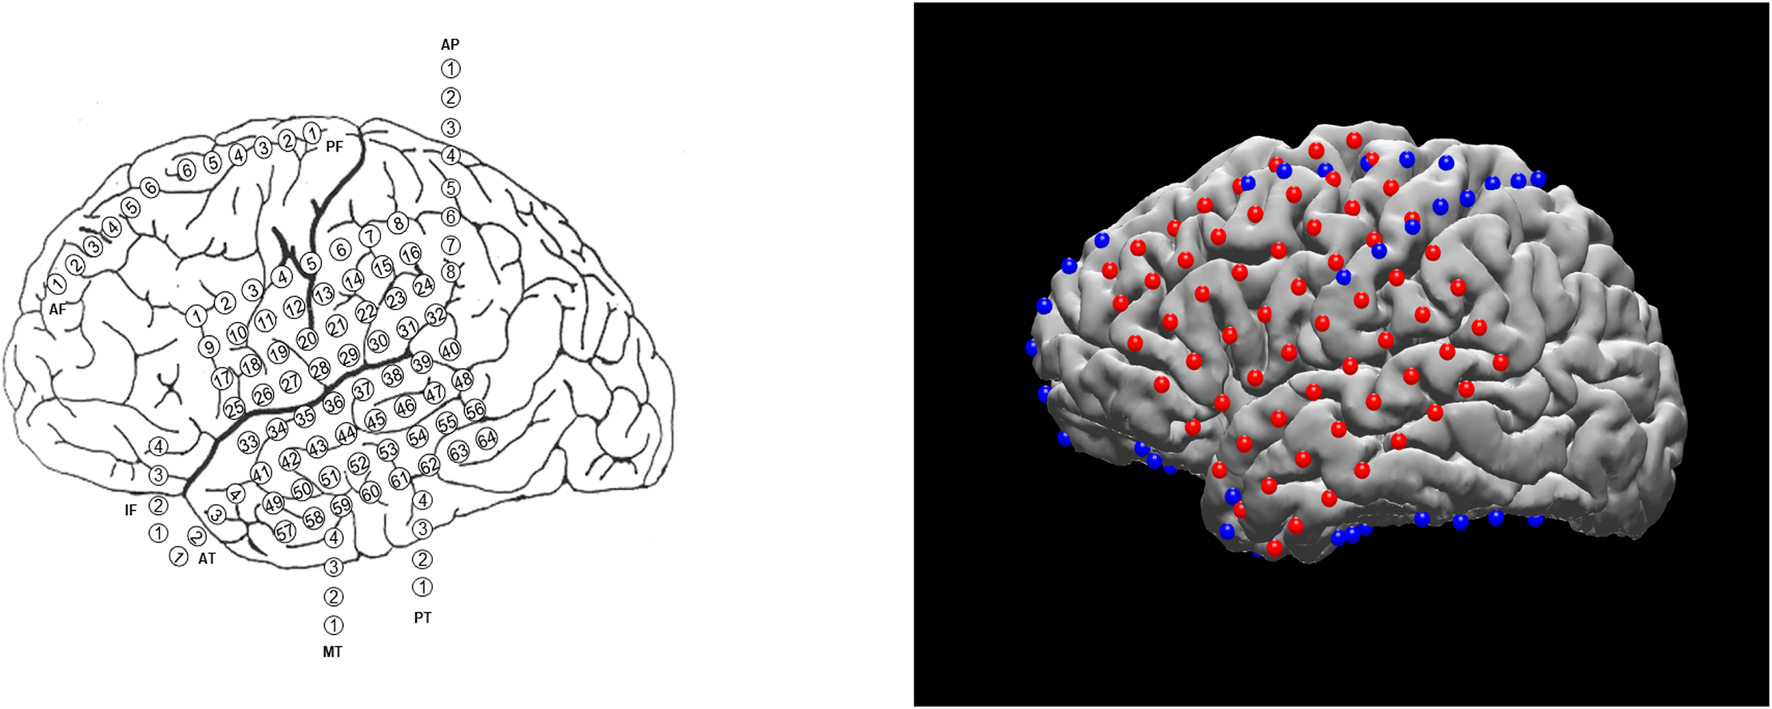

Planning the surgical approach to the treatment of drug-resistant focal epilepsy involves the integration of multiple sources of data to determine the brain areas to target for resection in order to maximize the chance of cure while minimizing the risks of neurological deficits. In many cases, neurologists and neurosurgeons employ intracranial electrodes to precisely identify sites of seizure initiation and spread as well as identify eloquent brain areas to avoid. In clinical practice, the spatial distribution of electrodes is first recorded manually by neurosurgeons, either via hand drawings or schematic plots (see example on the left of Figure 1). Although these raw materials serve as essential references for surgical planning, they are not intended to convey the precise anatomical locations of these electrodes. The clinicians must then mentally translate this two-dimensional data onto the complex three-dimensional structure of the patient’s own brain, in order to determine if the observed data supports their localization hypothesis (based the presence of brain lesions or the anatomical-clinical manifestation of the seizure) and then plan the best surgical approach (Jobst et al., 2020). There are limited visualization approaches for this data and most require specialized software for viewing and annotation. Using post-operative Computed Tomography (CT) or magnetic resonance imaging (MRI) scans coregistered to the pre-operative MRI, the physical location of electrodes can be registered directly to patient brains. The visual results of electrode localization procedures typically contain schematics of electrodes overlaid on an individual patient’s brain (for subject-level analyses) or a template brain (for group-level analyses). The right panel of Figure 1 shows an example electrode localization that was generated by the open-source toolkit, N-Tools-Elec (Yang et al., 2012).

Different visualization methods for the same ECoG data set. Left: a schematic drawing. Right: a static 2D figure from N-Tools-elec.